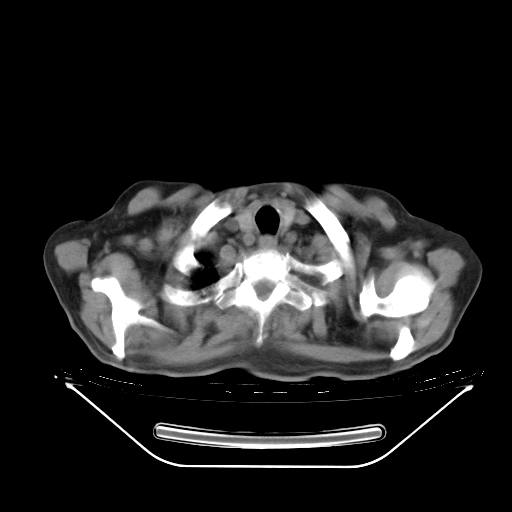

今天复查肺部CT,发现双肺广泛磨玻璃样改变。所以我把3月19日和5月9日相隔50天的肺部CT上传。请大家会诊。

5月9日肺部CT(在4月27日齐鲁医院肺部CT描述部分肺组织磨玻璃样改变,12天后肺组织广泛磨玻璃样改变)

2009年5月9日肺部CT

大致读了系列胸部CT:纵隔窗无明显异常,肺窗:从4、27至今:主要是双肺中下野外带可见毛玻璃样改变,目前处于急性肺泡炎阶段,至于原因考虑1、结替组织或胶原血管性疾病所致?2、恶性疾病如恶组在肺部所致的表现或细支气管肺泡癌?3、药物或其它原因如肺蛋白沉着症所致肺泡炎目前不太可能?总之,明天就去请我院的呼吸科、感染科、血液科和临免专家会诊哈。